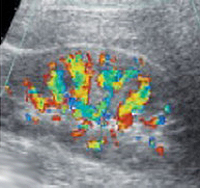

- УЗИ с допплерографией позволяет изучить кровообращение в почечных сосудах.

При проведении пробы Зимницкого выявляется изогипостенурия. УЗИ почек свидетельствует о снижении толщины паренхимы и уменьшении размера почек. Снижение внутриорганного и магистрального почечного кровотока выявляется на УЗДГ сосудов почек. Рентгенконтрастную урографию следует применять с осторожностью из-за нефротоксичности многих контрастных препаратов. Перечень других диагностических процедур определяется характером патологии, ставшей причиной развития ХПН.